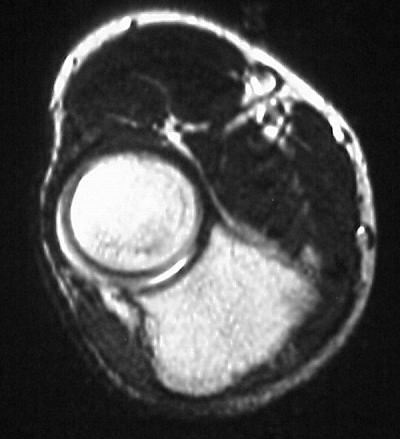

MRI shows an osteochondral sequestrum of the anterior capitellum:

Treatment options? Do nothing, Open reduction and bone graft, sequestrum excision or radial head excision. In this case, at surgery, the loose articular fragment was too thin to allow reliable fixation, and was simply excised.